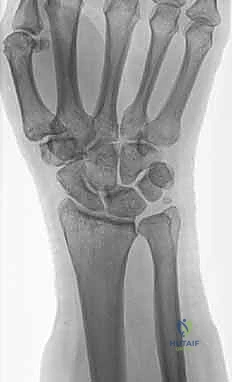

1. الأشعة السينية (X-rays): بوضعيات متعددة (أمامية خلفية، وجانبية دقيقة). الوضعية الجانبية الحقيقية (True Lateral) حاسمة لاكتشاف أي خلع جزئي في المفصل (DRUJ).

الأعراض والتشخيص السريري الدقيق مع الأستاذ الدكتور محمد هطيف

عند تعرض المريض لإصابة في الساعد أو المعصم، فإن سرعة التشخيص ودقته هما مفتاح العلاج الناجح. يتميز الأستاذ الدكتور محمد هطيف باتباع بروتوكول تشخيصي صارم يضمن عدم إغفال أي تفصيل صغير قد يؤثر على مستقبل وظيفة يد المريض.

الأعراض السريرية لكسور الزند

- ألم حاد ومفاجئ: خاصة عند محاولة تدوير الساعد (الكب والبسط).

- تورم وكدمات: تظهر بسرعة حول منطقة المعصم والجهة الزندية (جهة الإصبع الصغير).

- تشوه مرئي: في حالات الكسور المنزاحة، قد يبدو المعصم معوجًا أو غير متطابق مع شكله الطبيعي.

- علامة مفتاح البيانو (Piano Key Sign): وهي علامة سريرية هامة تدل على تمزق أربطة المفصل الزندي الكعبري البعيد (DRUJ). عند الضغط على رأس الزند البارز، فإنه ينزل لأسفل، وبمجرد إزالة الضغط، يرتد لأعلى مثل مفتاح البيانو.